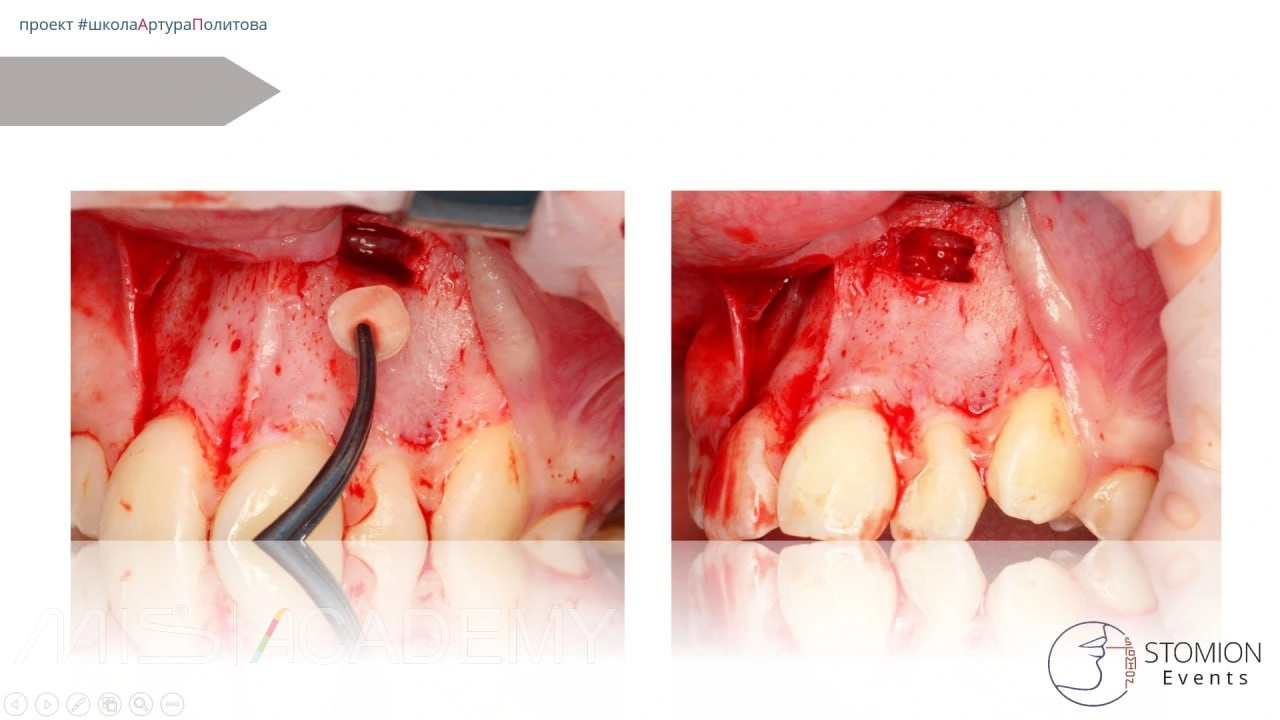

— Трепанация в области истонченного кортикала, чтобы не травмировать сосудистонервный пучок.

— Сегментация.

— Извлечение центральной части коронки, далее бугра, далее смещение зуба в просвет и сегментация по типу шинковки до полной экстракции.